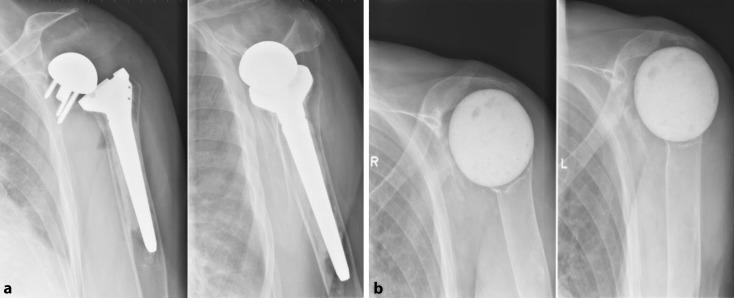

Indications for implantation of a megahead prosthesis were loosening RSA ( = 5), infection ( = 4), dislocation ( = 1) and nerve irritation ( = 1). Improvement of range of motion was observed. Anterosuperior migration of the prosthesis was noted in 2 patients. Another 2 patients were ultimately revised to RSA. Seven permanent spacers were implanted for infection, of which 2 remain in place till today. The other 5 were revised to RSA. Of the 5 patients treated with RA, 3 were revised further on to RSA, resulting in pain relief and regain of function.

植入大头假体的指征包括RSA松动(n = 5)、感染(n = 4)、脱位(n = 1)和神经刺激(n = 1)。观察到活动范围有所改善。2例患者出现假体前上移位。另外2例患者最终翻修至RSA。因感染植入了7个永久性间隔物,其中2个至今仍在位。另外5个翻修至RSA。在接受RA治疗的5例患者中,3例进一步翻修至RSA,疼痛缓解且功能恢复。